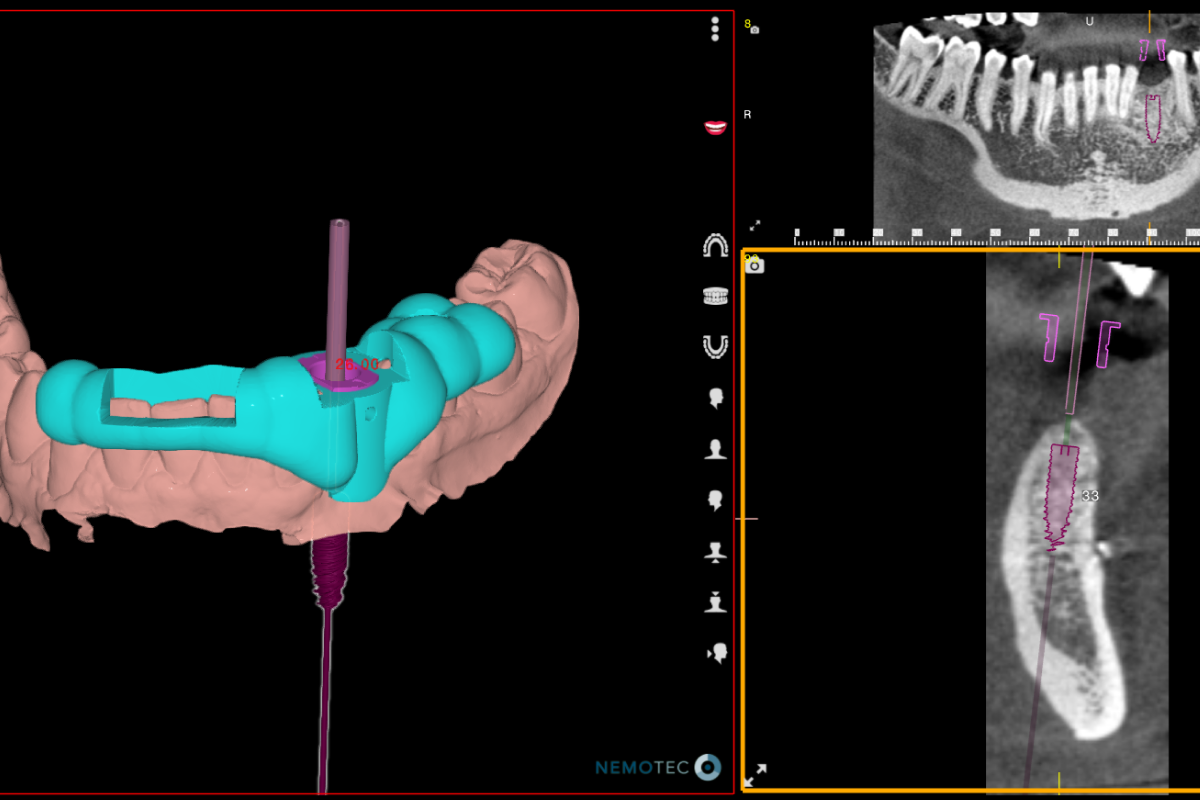

Chirurgie guidée

Un système permettant l’impression en 3 dimensions de guides chirurgicaux sur-mesure afin de permettre au praticien de pouvoir planifier avec précision les opérations.